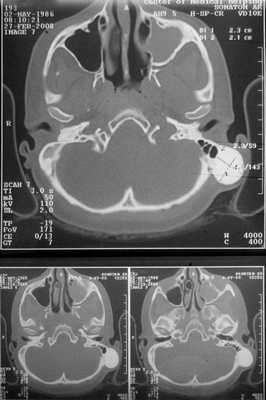

Больная консультирована нейрохирургом, невропатологом, окулистом. В неврологическом статусе патологических изменений не выявлено. Обнаружена ангиопатия сетчатки обоих глаз с венозным полнокровием. Проведена компьютерная томография височных костей. На серии томограмм получены изображения височных костей нормальной пневматизации, слева в задних отделах сосцевидного отростка крупноячеистое строение. По заднему краю левого сосцевидного отростка отмечается утолщение кости с четкими округлыми контурами, гомогенной структуры, без мягкотканного компонента, гиперинтенсивной плотности до +1600 ед.Н. Наружный и внутренний слуховые проходы с обеих сторон не деформированы, нормальных размеров, с четкими контурами, патологических включений в области внутреннего уха не выявлено.

Заключение: КТ-признаки остеомы сосцевидного отростка левой височной кости (рис. 2). Рисунок 2. КТ остеомы сосцевидного отростка височной кости.